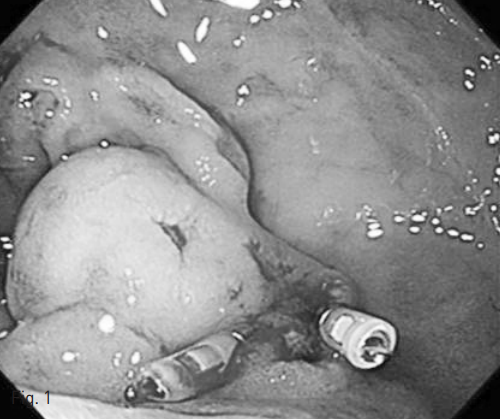

Sheath를 통하여 추가로 2번째 microcatheter를 장간막신장정맥단락의 중간 부위까지 진입시킨 후에 유출정맥을 Interlock Detachable Coil (Boston Scientific) 4ea, Nester coil (Cook Medical) 6ea로 색전술을 시행함 (Fig. 3B).

Fig. 3

B. Embolization with microcoils (open arrow) was done for draining vein of mesenterorenal shunt which is distal to duodenal varix.